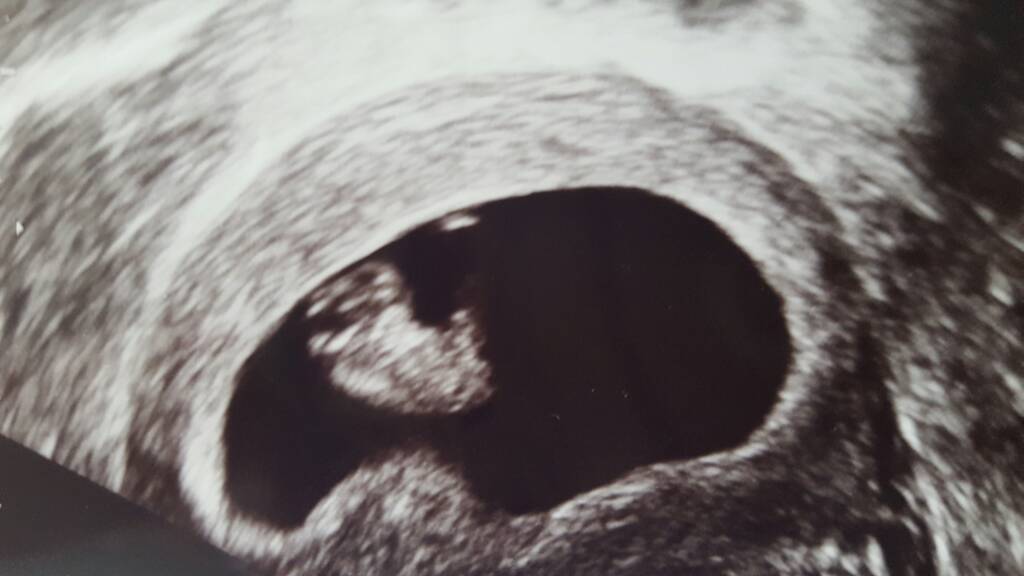

Oto moj Skarbma 18.76 mm, słychać mu serduszko i termin na 6.06 dokładnie tak jak sobie wyliczylam